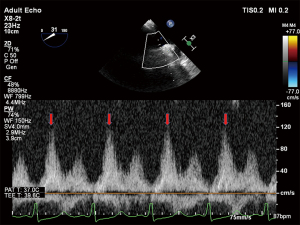

Twelve-lead electrocardiogram showed ST-T segment depression and signs of left ventricular hypertrophy. Transthoracic echocardiography (TTE) showed asymmetric septal hypertrophy with a maximal wall thickness of 16 mm at the LVOT level. Transesophageal echocardiography (TEE) revealed significant SAM of the anterior mitral leaflet (Figure 1, Video 1), causing dynamic LVOT obstruction (Figures 2,3) and severe MR (Figure 2, Video 2). On Valsalva maneuver, the LVOT pressure gradient reached 233 mmHg. Her left atrium was dilated and pulmonary artery systolic pressure was elevated. Reversed systolic wave was observed in the pulmonary vein flow (Figure 4). No abnormal muscle bundles were observed on imaging, including TEE and TTE.

Following implantation, TEE revealed significant improvement with only mild residual MR. The residual mitral valve orifice area was 1.6 cm2, and the mean diastolic trans-mitral pressure gradient increased to 4 mmHg. The LVOT gradient decreased to 81 mmHg. Invasive hemodynamic monitoring showed left atrial pressure dropped significantly from 55 mmHg pre-procedure to 25 mmHg post-procedure. Pulmonary vein flow spectrum normalized (Figure 5).